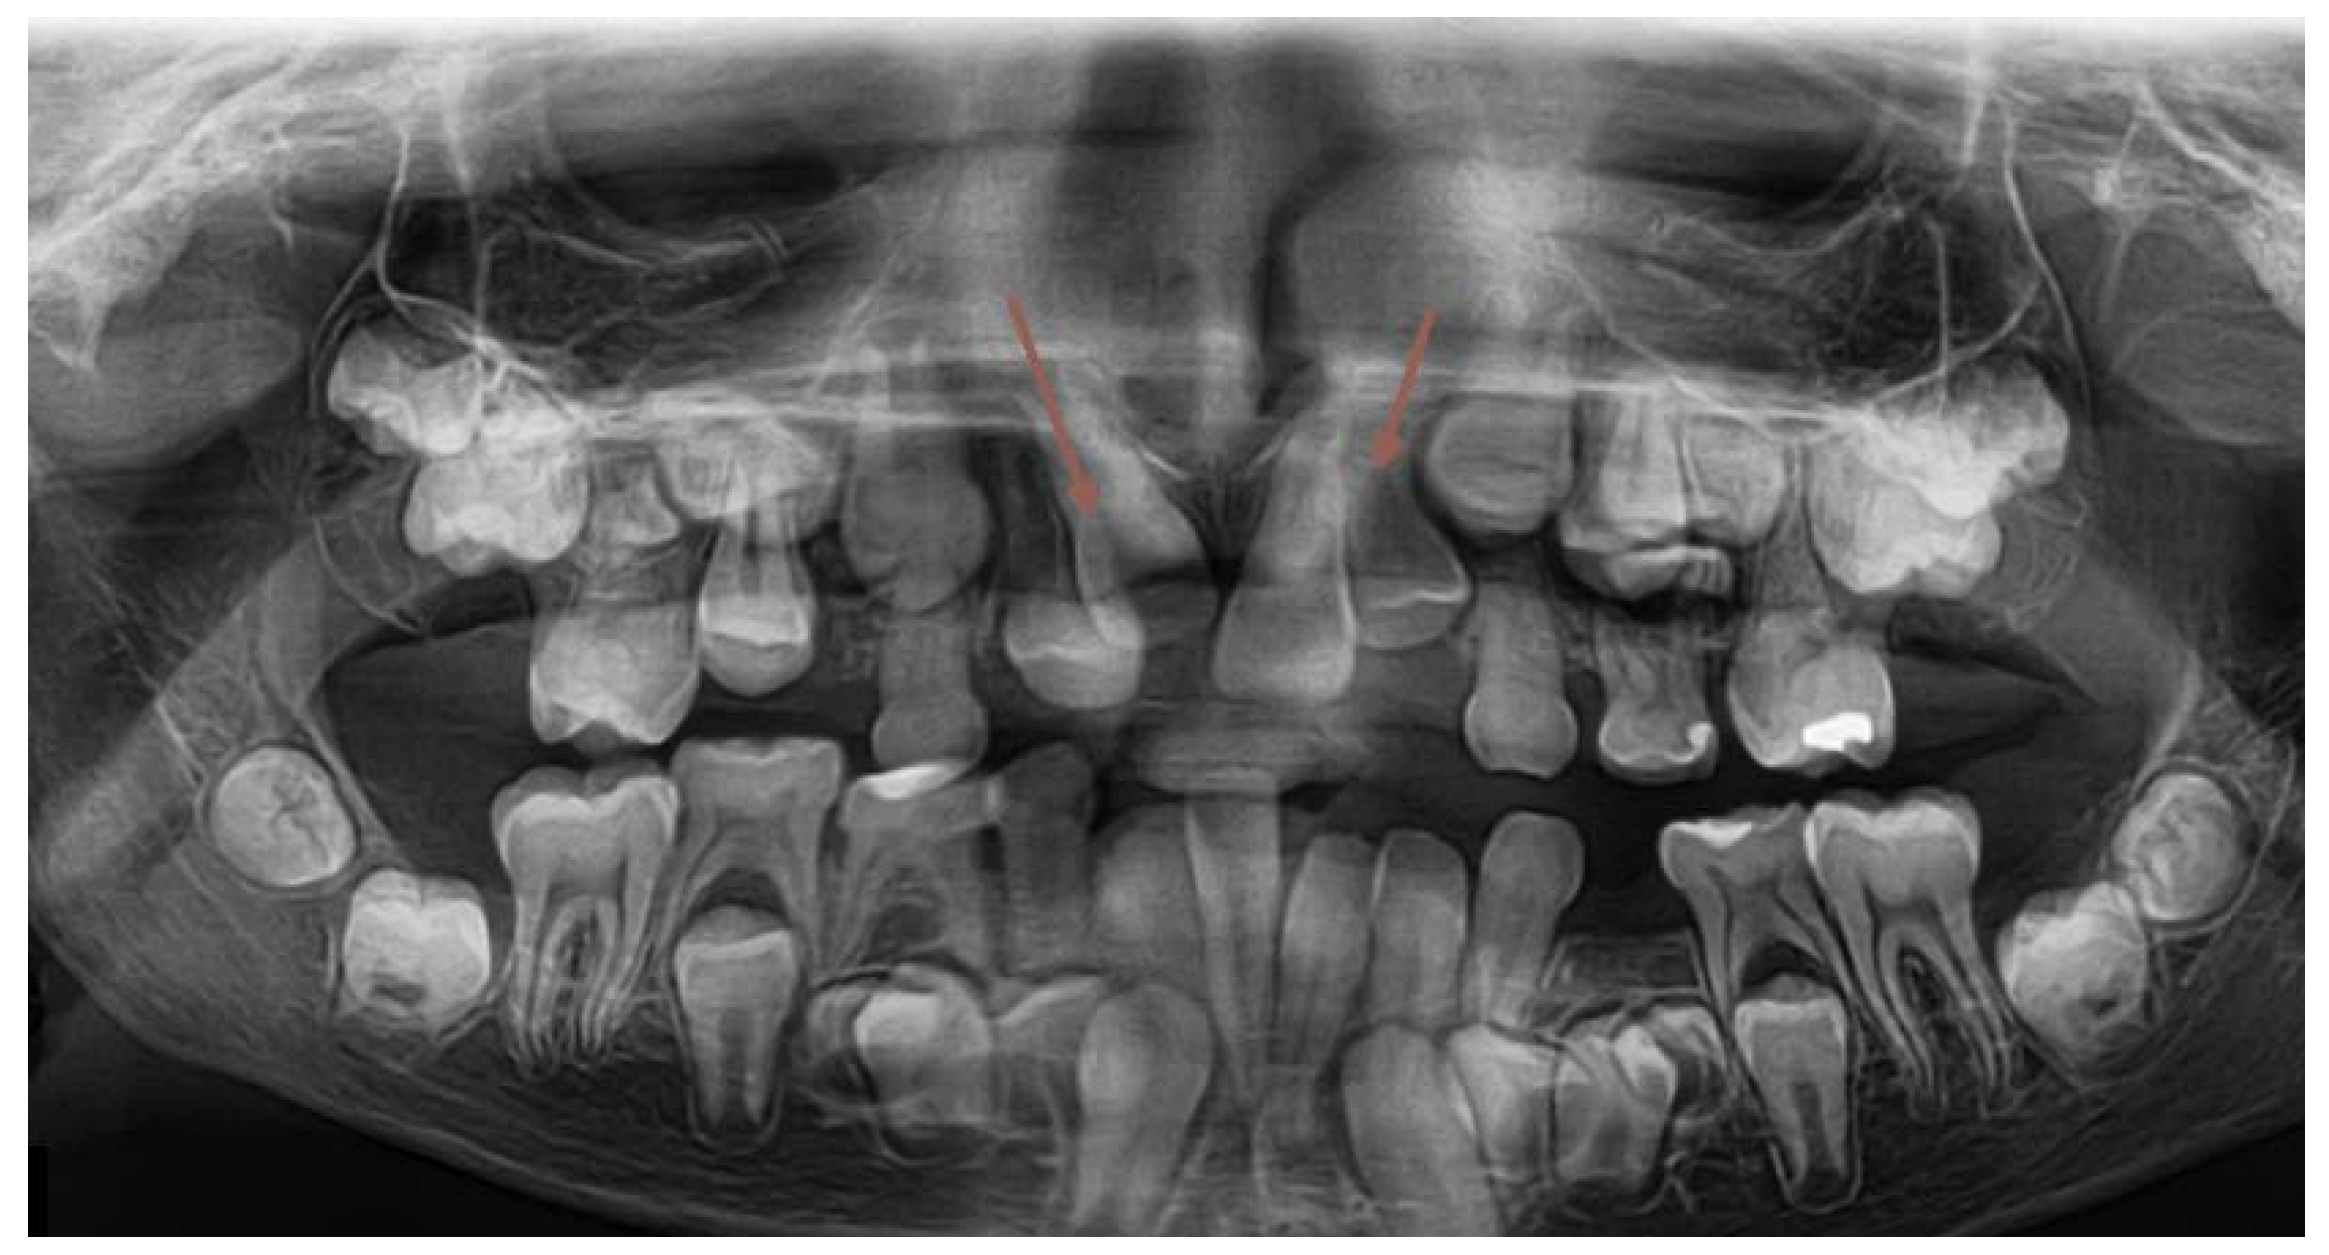

The next two OPG x-rays were taken after 11 months. On the latter (2017) (Figure 5) it became clear, that 22 and 11 were inhibited in eruption. ( DA 9,1 and 9,3, CA 12 y 11 mths) The patient was referred to the second CBCT scan image reproduction to make clear the underlying surgical situation. (Figure8). The CBCT scan revealed the position of supernumerary teeth also in the lower dental arch. (Figure 8.,9.)

Figure 5. The follow-up OPG x-ray – taken in 2017.